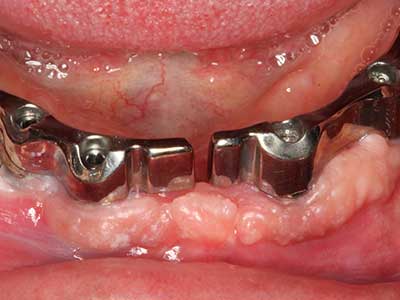

Фиг. 13: Подходяща иригация с остатъчна 4 mm дебелина на костта е важна за този 52-годишен пациент по време на разделянето на костта.

Фиг. 14: Поставяне на RSX имапланта (Bego Implant Systems, Bremen).

Фиг. 15: Прегледът на рентгеновата снимка след 1 година показва стабилно състояние на нивото на костта.

Фиг. 16: Интраоралните условия също са стабилни с поставените импланти в кератизираната гингива.